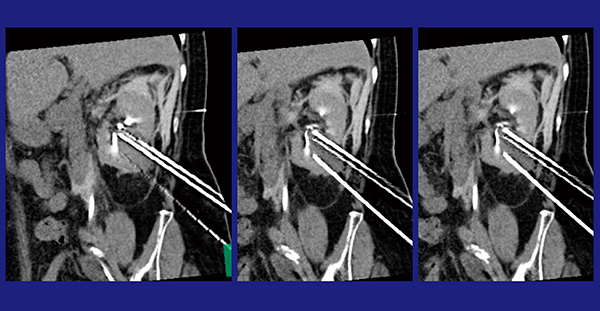

3)IVR-CTによる経皮的アブレーション治療(凍結療法)

当院では,2014年から凍結療法を導入している。対象はT1a,4cm以下の腎細胞がんで,治療には冷凍手術器を用いる。高圧ガスのジュール・トムソン効果による急速凍結でアイスボールを形成し,細胞障害や血流うっ滞によって腫瘍を障害する。治療に当たってはCT透視下で凍結針を進め,術中もCTを撮影することでアイスボールの確認を行い,下行結腸など周辺臓器を損傷しないように治療を行っている。症例4は,右腎下極に4cmを超える腎がん(cT1b)があり,頭尾方向に長く,腎洞内への突出もある症例で穿刺難易度が高かったが,CT透視により多断面で針先を確認することで,ぎりぎりまで針先を進めてしっかりと治療することができた(図7)。

図7 症例4:腎がんの凍結療法

多断面による穿刺針の確認で頭尾方向に長い腫瘍を確実に穿刺